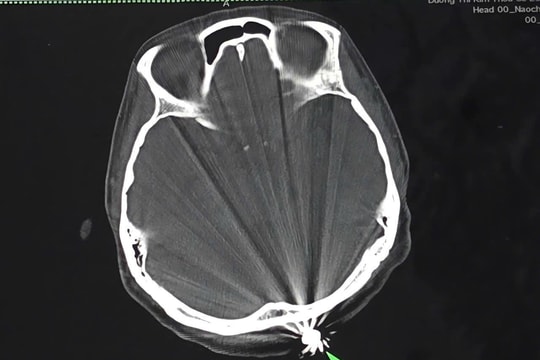

Phẫu thuật thành công cho phụ nữ bị viên đạn lạc găm vào đầu khi đang làm vườn

Khi đang làm vườn tại nhà, một phụ nữ 40 tuổi ở Cần Thơ bất ngờ bị viên đạn lạc găm vào vùng đầu. May mắn được xử trí kịp thời, dị vật đã được lấy ra an toàn, hiện sức khỏe bệnh nhân đã ổn định.